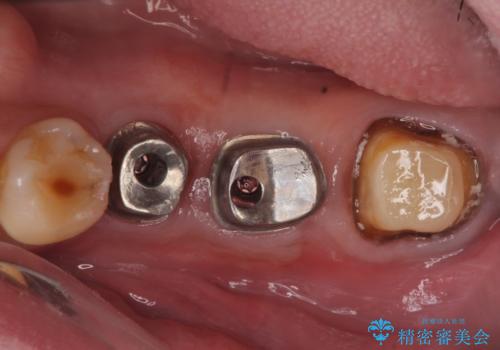

欠損部位である左下5、6番目にインプラントを埋入し、オールセラミッククラウンによる補綴を行いました。

カスタムアバットメントについて

カスタムアバットメントは患者様それぞれの歯茎に合わせて製作されたオーダーメイドのアバットメントです。

既製のアバットメントに比べ適合がよく、高い清掃性を誇ります。